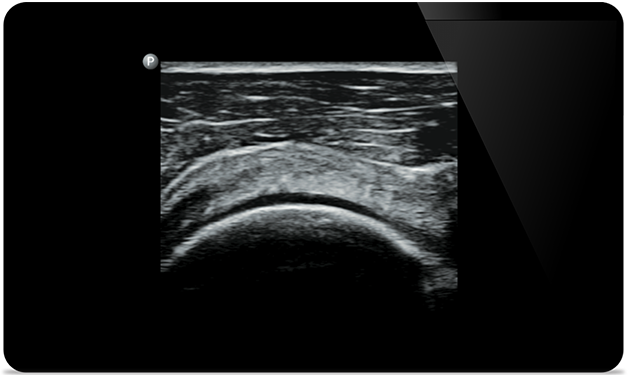

Lumify vă ajută să vedeţi detaliile fine ale muşchilor, articulaţiilor, ligamentelor, tendoanelor şi cartilagiilor pentru a pune un diagnostic mai precis al leziunilor.

Lumify vă poate ajuta să evaluaţi pacienţii din cap până în picioare, fie că este vorba de fasceită plantară, tendinită sau bursită la nivelul tendonului rotulian, sau chiar de instabilitatea umărului la nivelul centurii scapulare.